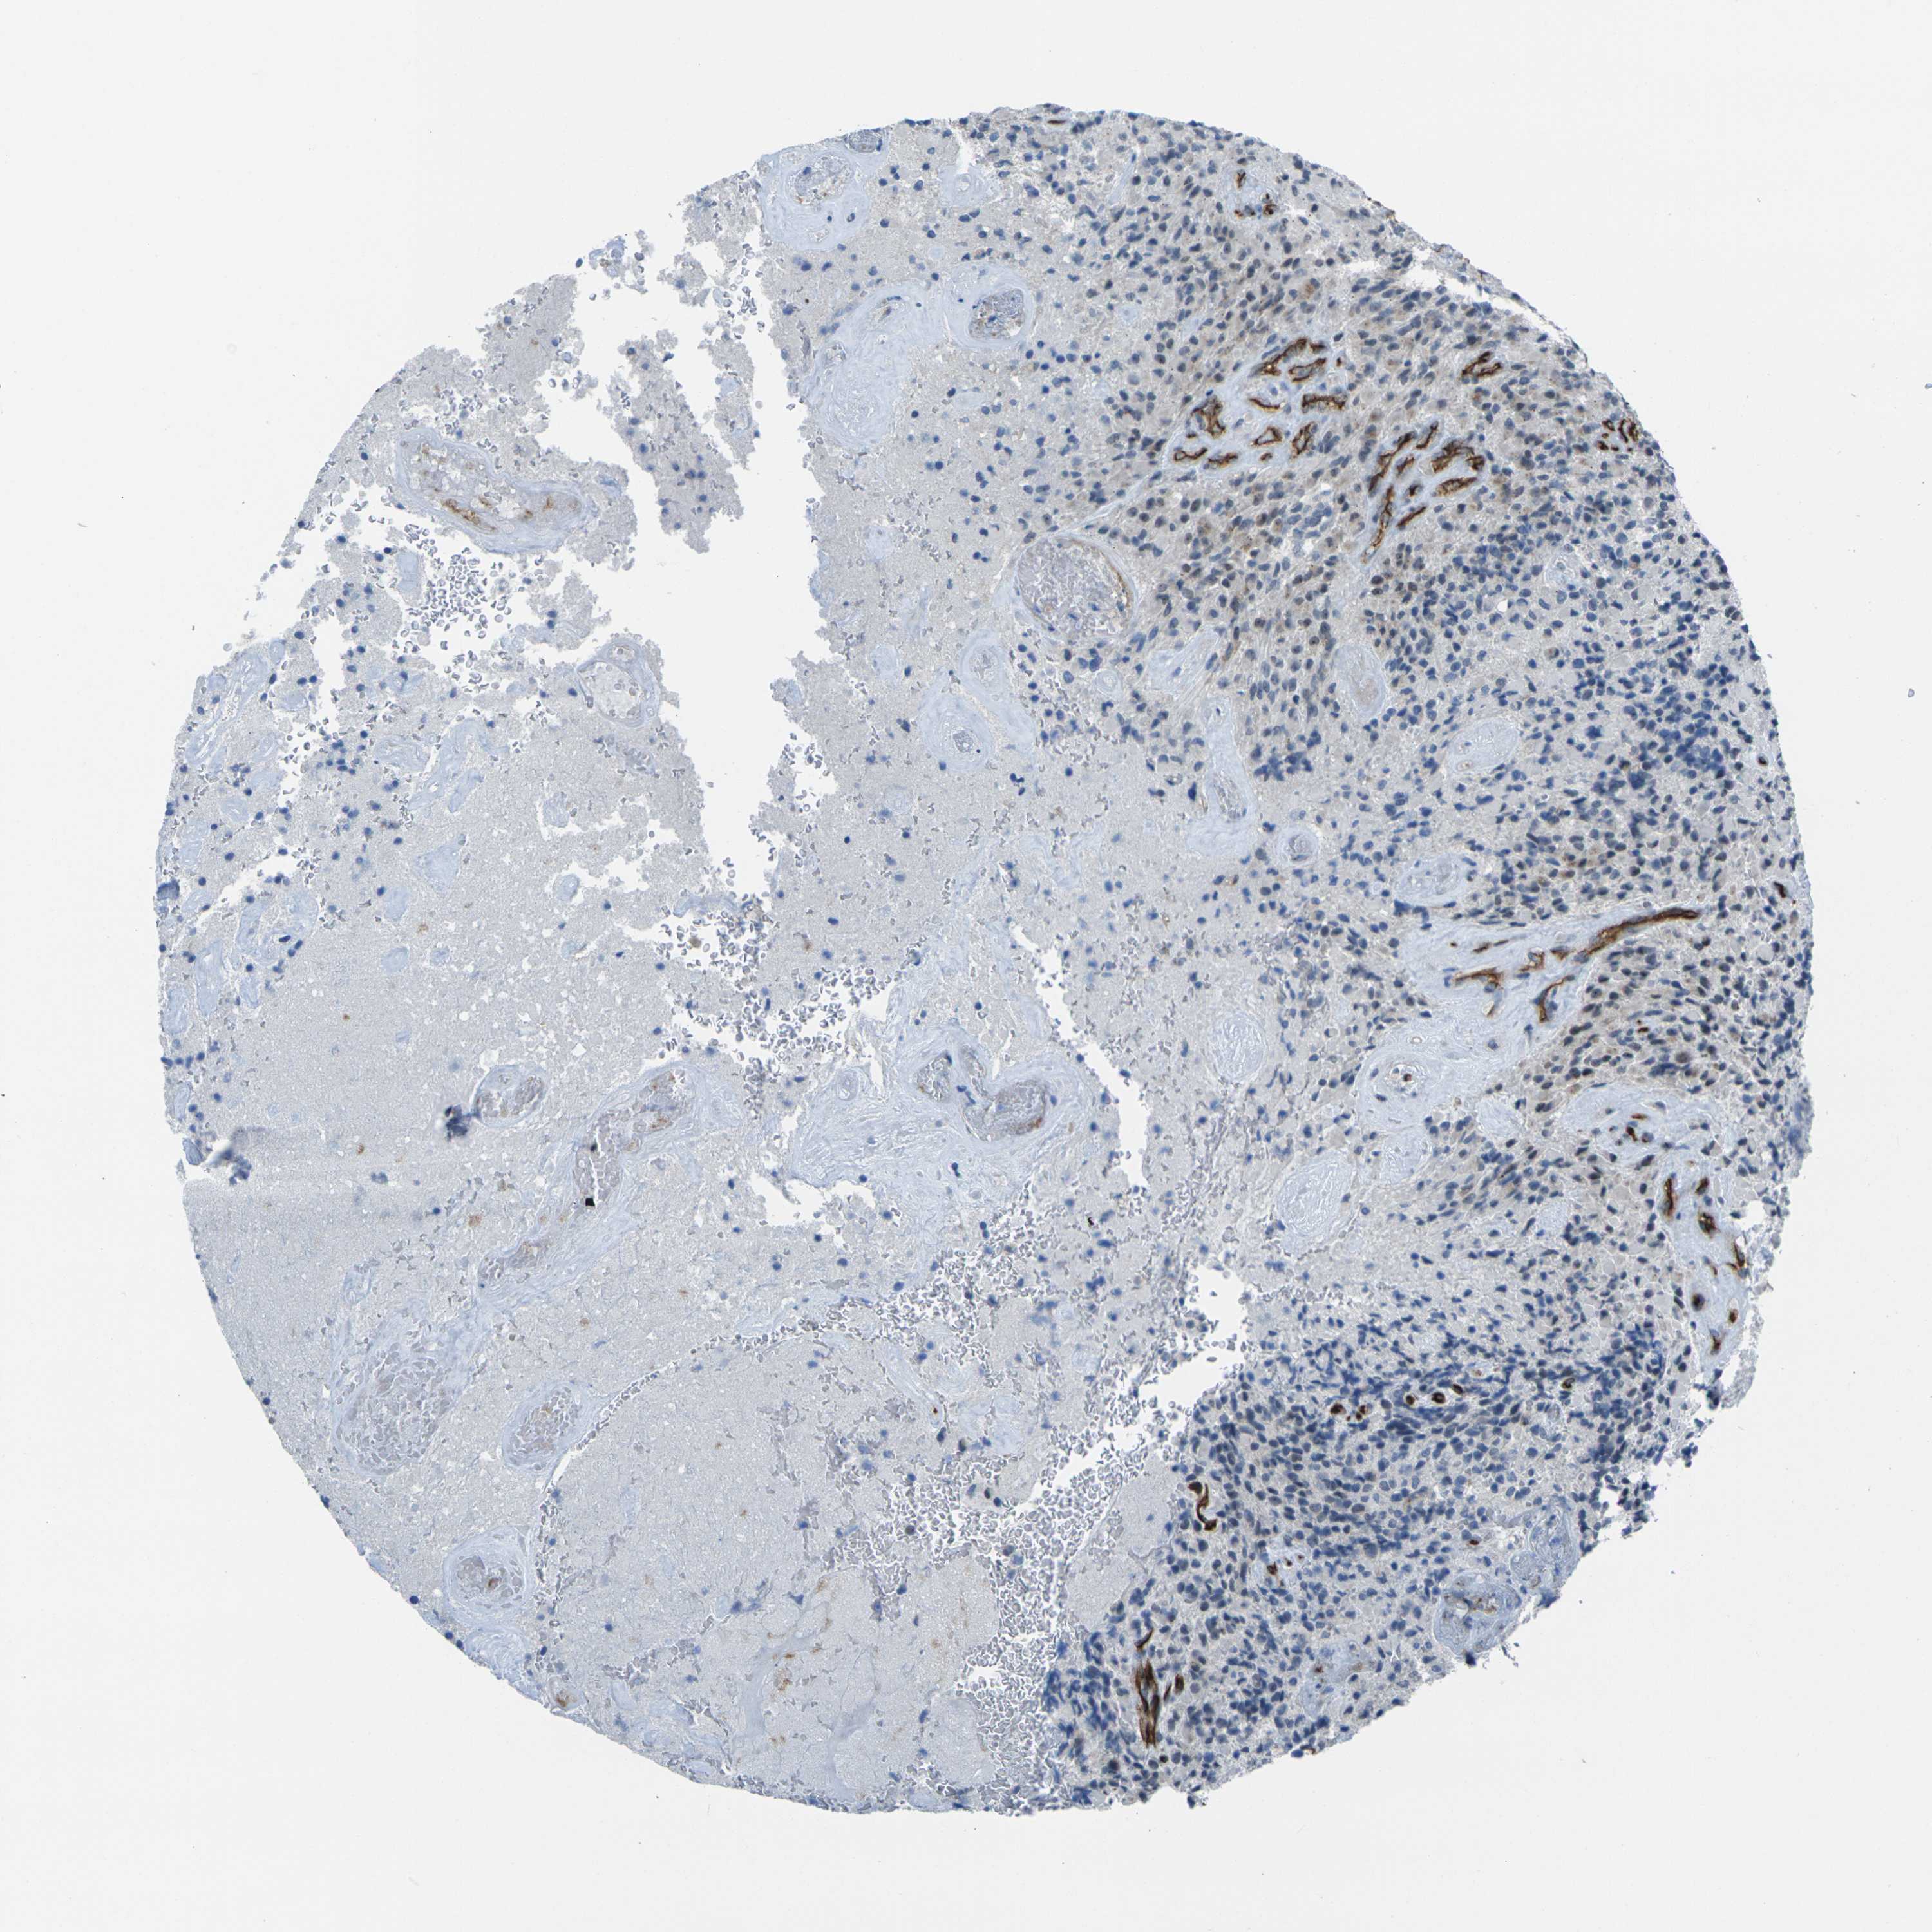

GLIOMA - Protein expressioni

A mouse-over function shows sample information and annotation data. Click on an image to view it in a full screen mode. Samples can be filtered based on level of antibody staining by selecting one or several of the following categories: high, medium, low and not detected. The assay and annotation is described here.

Note that samples used for immunohistochemistry by the Human Protein Atlas do not correspond to samples in the TCGA dataset.

Antibody stainingi

Antibody staining in the annotated cell types in the current human tissue is reported as not detected, low, medium, or high, based on conventional immunohistochemistry profiling in selected tissues. This score is based on the combination of the staining intensity and fraction of stained cells.

Each image is clickable and will lead to virtual microscopy that enables deeper exploration of all samples and also displays staining intensity scores, fraction scores and subcellular localization as well as patient and tissue information for each sample.

Antibody HPA013659

Antibody HPA015639

Glioma, malignant, High grade

Glioma, malignant, Low grade